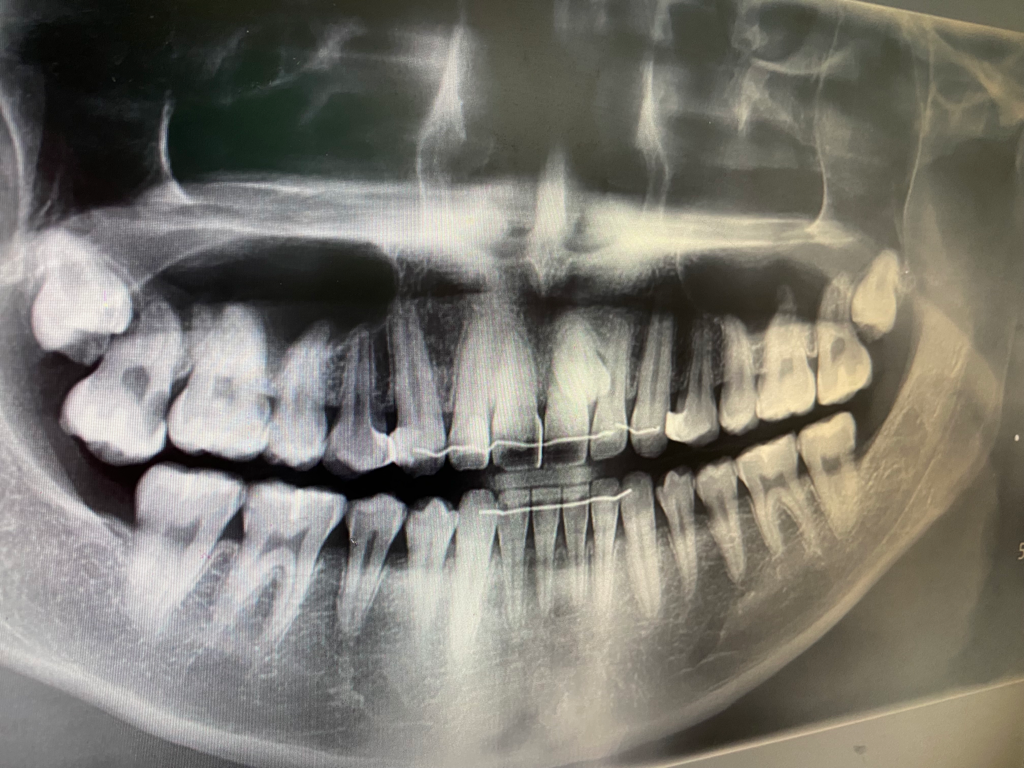

사진 기준 왼쪽 위 어금니에 신경치료를 받습니다.

사진상으로는 치근단농양이 없어보이지만, 임상진료는 항상 변이가 있고 예측대로 흘러가지 않는경우도 있기때문에, 치과측과 상담을 받아보시기 바랍니다 감사합니다.